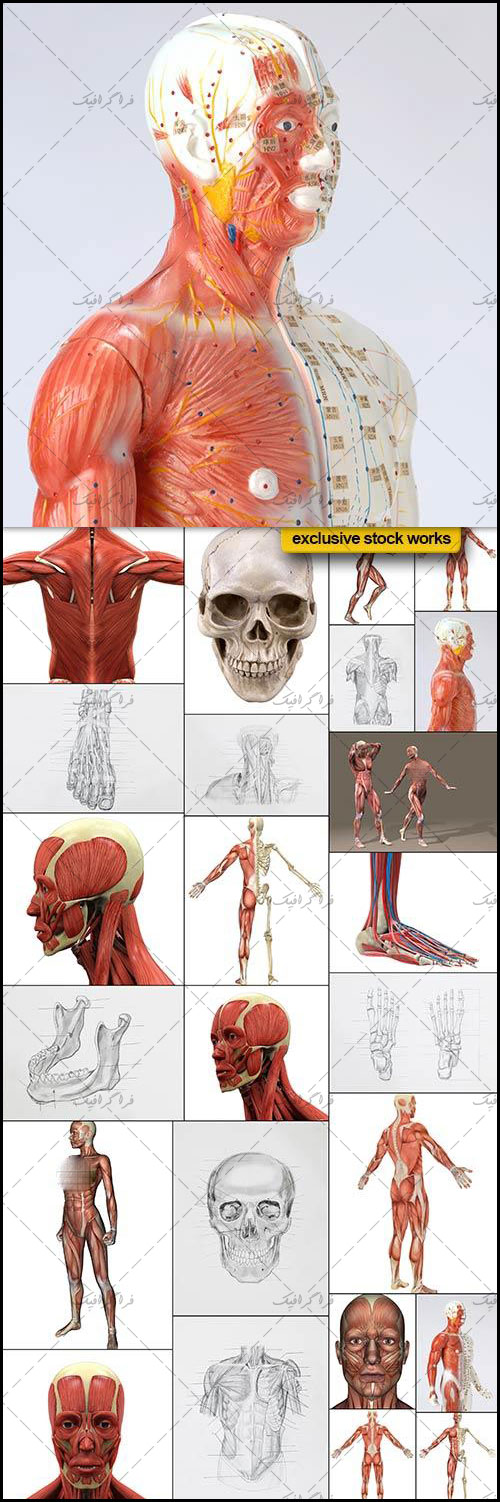

دانلود عکس اسکلت انسان دانلود عکس آناتومی بدن خانم از پشت و جلو دانلود عکس باکیفیت جمجمه انسان.

عکس اسکلت بدن انسان با کیفیت. عکس اسکلت عکس اسکلت برای پروفایل عکس اسکلت انسان عکس اسکلت خفن عکس اسکلت بدن انسان با کیفیت عکس اسکلت بدن انسان عکس اسکلت ترسناک عکس اسکلت فانتزی عکس اسکلت فانتزی دخترانه پرچم عکس اسکلت. عکس با کیفیت اسکلت داخلی انسان و درد و گرفتگی در ناحیه استخوان زانو ویژه استفاده در امور تبلیغاتی و تجاری طراحی کاتالوگ بروشور و تراکت با موضوع پزشکی فیزیوتراپی ارتوپد دکتر روماتیسم فیریوتراپ طب فیزیکی. عکس اسکلت بدن انسان زن و مرد آناتومی ساتین 16 سپتامبر 2017. اسکلت داربست بدن است تمام قسمت های بدن روی اسکلت قرارگرفته اند بدن انسان از ۲۰۶ قطعه استخوان تشکیل شده است این استخوان ها طوری با نظم کنار هم قرار گرفته اند که انسان را قادر می سازد حرکات دقیقی داشته باشد.

اسکلت جمجمه و گردن انسان ستون فقرات آناتومی اسکلت جمجمه و گردن انسان ستون فقرات آناتومی تصویر با کیفیت را از لینک زیر می توانید دانلود کنید. ۱ مطلب با کلمه ی کلیدی عکس اسکلت بدن انسان با کیفیت ثبت شده است گالری نسیم جدید ترین و با کیفیت ترین عکس های مناسبتی. عکس با کیفیت آناتومی اسکلت بدن انسان و درد و دیسک در قسمت مهره های ستون فقرات کمر ویژه استفاده در امور تبلیغاتی و تجاری طراحی کاتالوگ بروشور و تراکت با موضوع بیمارستان ها و کلینیک ها و درمانگاه ها و مطب ها پزشکان و.